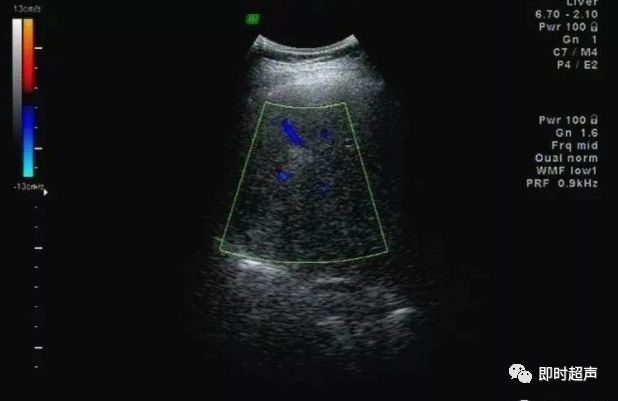

非均匀性脂肪肝:脂肪肝形成和发展过程中,受到门静脉血流中胰岛素和胰高血糖素含量以及肝内门静脉-体腔静脉交通支等因素的影响,脂肪浸润可表现为非均匀性。

依据超声表现可分为四型:

1、局灶浸润型:呈局灶性强回声,无包膜,边界不清,后方可伴衰减。

此型需与肝转移癌及肝血管瘤鉴别。

2、多灶浸润型:在回声相对正常的肝内,可见多发强回声。

3、叶段浸润型:一部分区域为低回声,其它区域为强回声。

此型需与肝转移癌鉴别,此型肝内血管走行正常,无靶环征及牛眼征。

4、正常肝残留型:肝脏弥漫性回声增强,其内可见低回声区,为轻度脂肪浸润或性对正常肝残留区,好发于胆囊床、门静脉主干周围。